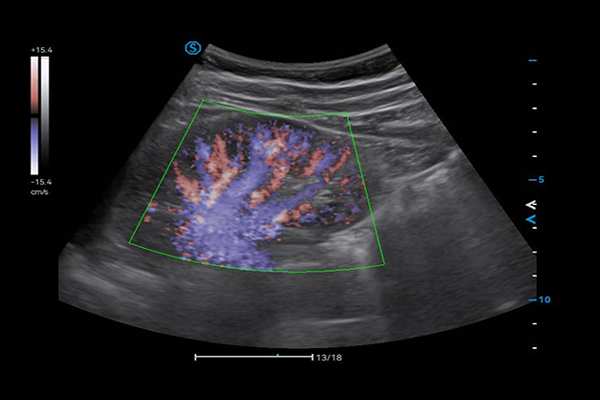

- Category: Color Doppler

Click on images to enlarge

VS Flow is highly sensitive to low velocity blood flow signal and especially suitable for superficial blood flow examination